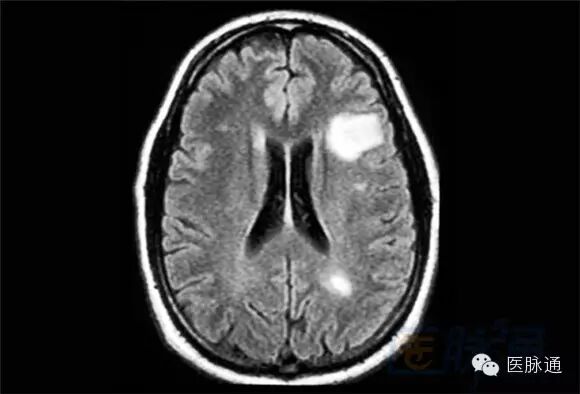

MS 的诊断是根据临床症状及辅助检查结果。一些临床医生使用2010年修订McDonald标准,该标准是结合临床症状、影像学检查和特异性检查来诊断MS 的。虽然血液和脑脊液对排除患者神经系统症状的其它病因是有价值的,但大脑、脊髓MRI仍然是帮助确定症状相关诊断和监测病情进展的首选检查。对比T1相 和FLAIR相(液体衰减反转恢复),MS斑块在T2相显示高信号(如图所示)。T1加权成像检测MS病变不太敏感,但它可以对慢性MS全脑萎缩情况进行 极好的全面评估。因为存在水肿和炎症,脱髓鞘病变有时与脑肿瘤相似。